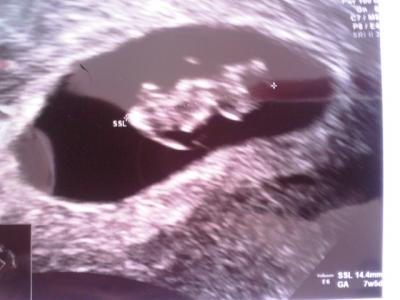

so mädels bin wieder da. alsoo krümel geht es supiii,herzchen hat dolle geschlagen. schön gewachsen und alles soo wie es sein muss. der erste grosse ultraschall hab ich dann am 15.9 ET ist der 26.3.11 und ab sonntag bin ich in der 9ssw :-)) achja hab den FA gewechselt und war echt super zufrieden. liebe glückliche grüsse Désirée

Bild zu Zurück vom FA - Forum für März - Mamis

Wunderbar! Schön, dass dieses Mal alles so gut läuft. Und ien schönes Bild hat du auch bekommen... LG Tina